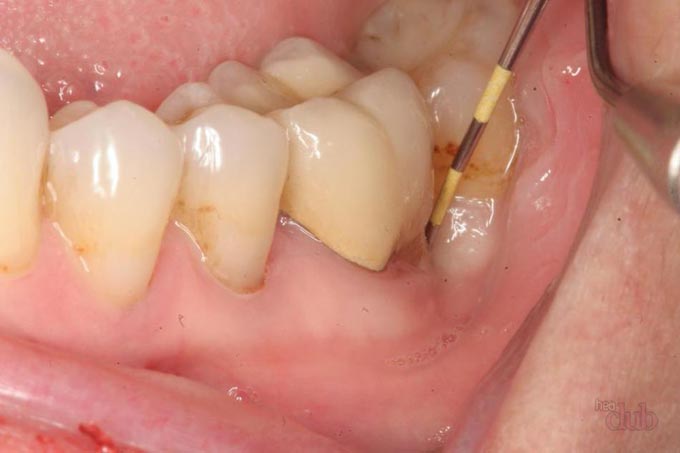

- осмотр (проходит в манипуляционном кабинете, процедурной, так как необходима стерильность) – врач оценивает отделяемое и глубину уплотнения ткани, зондирует ход, нередко можно увидеть и кончик нити в просвете, ее осторожно подтягивают и при возможности удаляют;

- УЗИ лигатурного свища – помогает определить его направление и форму, расположение нитки, состояние соседних тканей и органов, под контролем УЗИ хирургу иногда удается устранить шовный материал;

- фистулография – в свищевой ход вводят контраст и делают серию рентгеновских снимков в разных проекциях.

Фистулография лигатурного свища При зондировании свища трудно точно проследить ход, а также его возможную связь с глубокими полостями, наличие ветвей, есть риск травмирования. При фистулографии недостатком является лучевая нагрузка. Поэтому УЗИ признано самым безопасным методом, в последнее время его проводят после введения антисептической жидкости (например, Фурацилина).

Раствор будет своеобразным контрастным веществом, он позволяет более точно определить протяженность свища, его форму и взаимосвязь с соседними тканями.